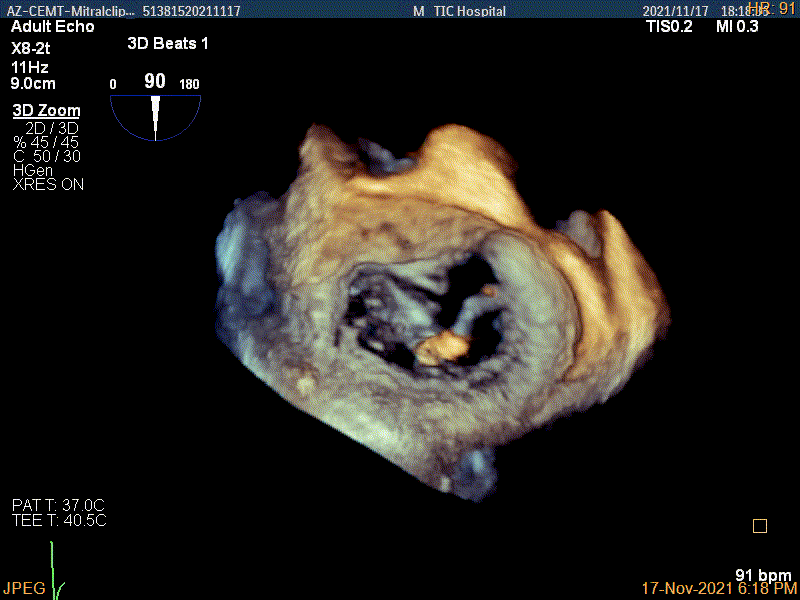

3D视图下进夹子并建立trajectory

3D视图打开夹子

3D视图下进第二个夹子并建立trajectory

3D视图两个夹子近似并排排列